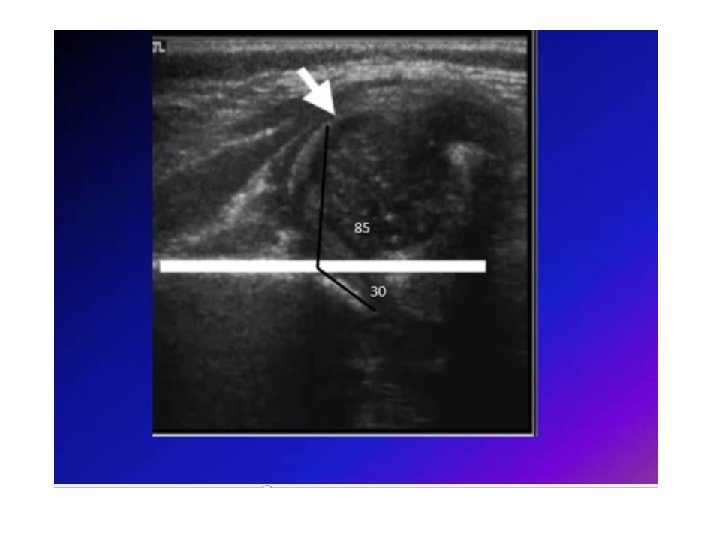

Developmental dysplasia of the hip (DDH) • Developmental dysplasia (abnormal development) of the hip refers to a variety of conditions where the femoral head and the acetabulum are improperly aligned. Previously known as congenital dislocation. Occur as a result of abnormal development of the hips during fetal development, more in female than male. • These conditions include dislocation (displacement of the bone from its normal position in a joint), subluxation (partial dislocation), and acetabular dysplasia.

• How to assess : • a. Positive Barlows test: ( Ortolan’s sign) click heard on abduction of thighs. • b. Shorting of limb on the affected side. • c. Asymmetrical thigh and gluteal folds. • d. Restriction of abduction. • e. After walking begins waddling gait in (bilateral) or limping in (unilateral).